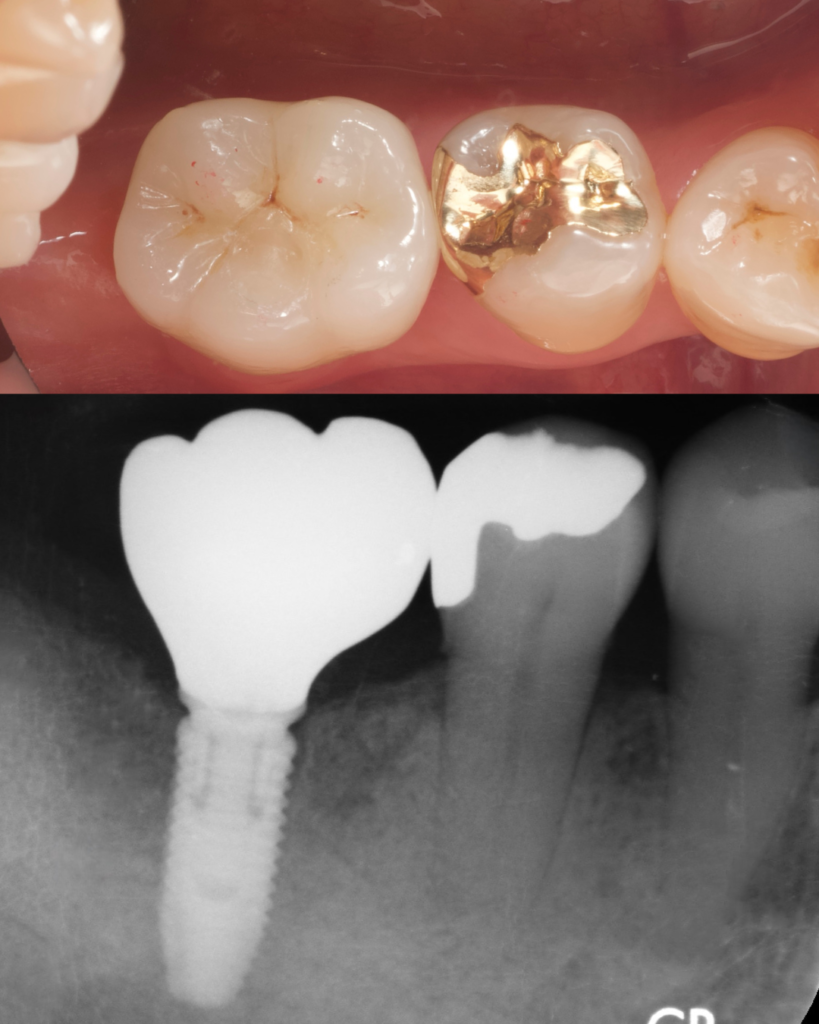

同様の費用と期間で右下の奥歯1本をインプラント治療した患者様です。

どの歯がインプラントだと思いますか?⠀左の奥歯がインプラントです。

天然歯と見分けがつかないよう、形態・色・咬合接触まで精密に再現しました。

下のレントゲンは、同じ症例の内部構造です。上の写真と一致しており、インプラント体と骨がしっかりと結合している状態が確認できます。

見た目だけでなく、CTによる3Dシミュレーションと設計精度によって、「美しさ」と「機能性」を両立しています。

フォーエバーデンタルクリニックでは、”どれがインプラントかわからない”その自然さを、治療の基準としています。